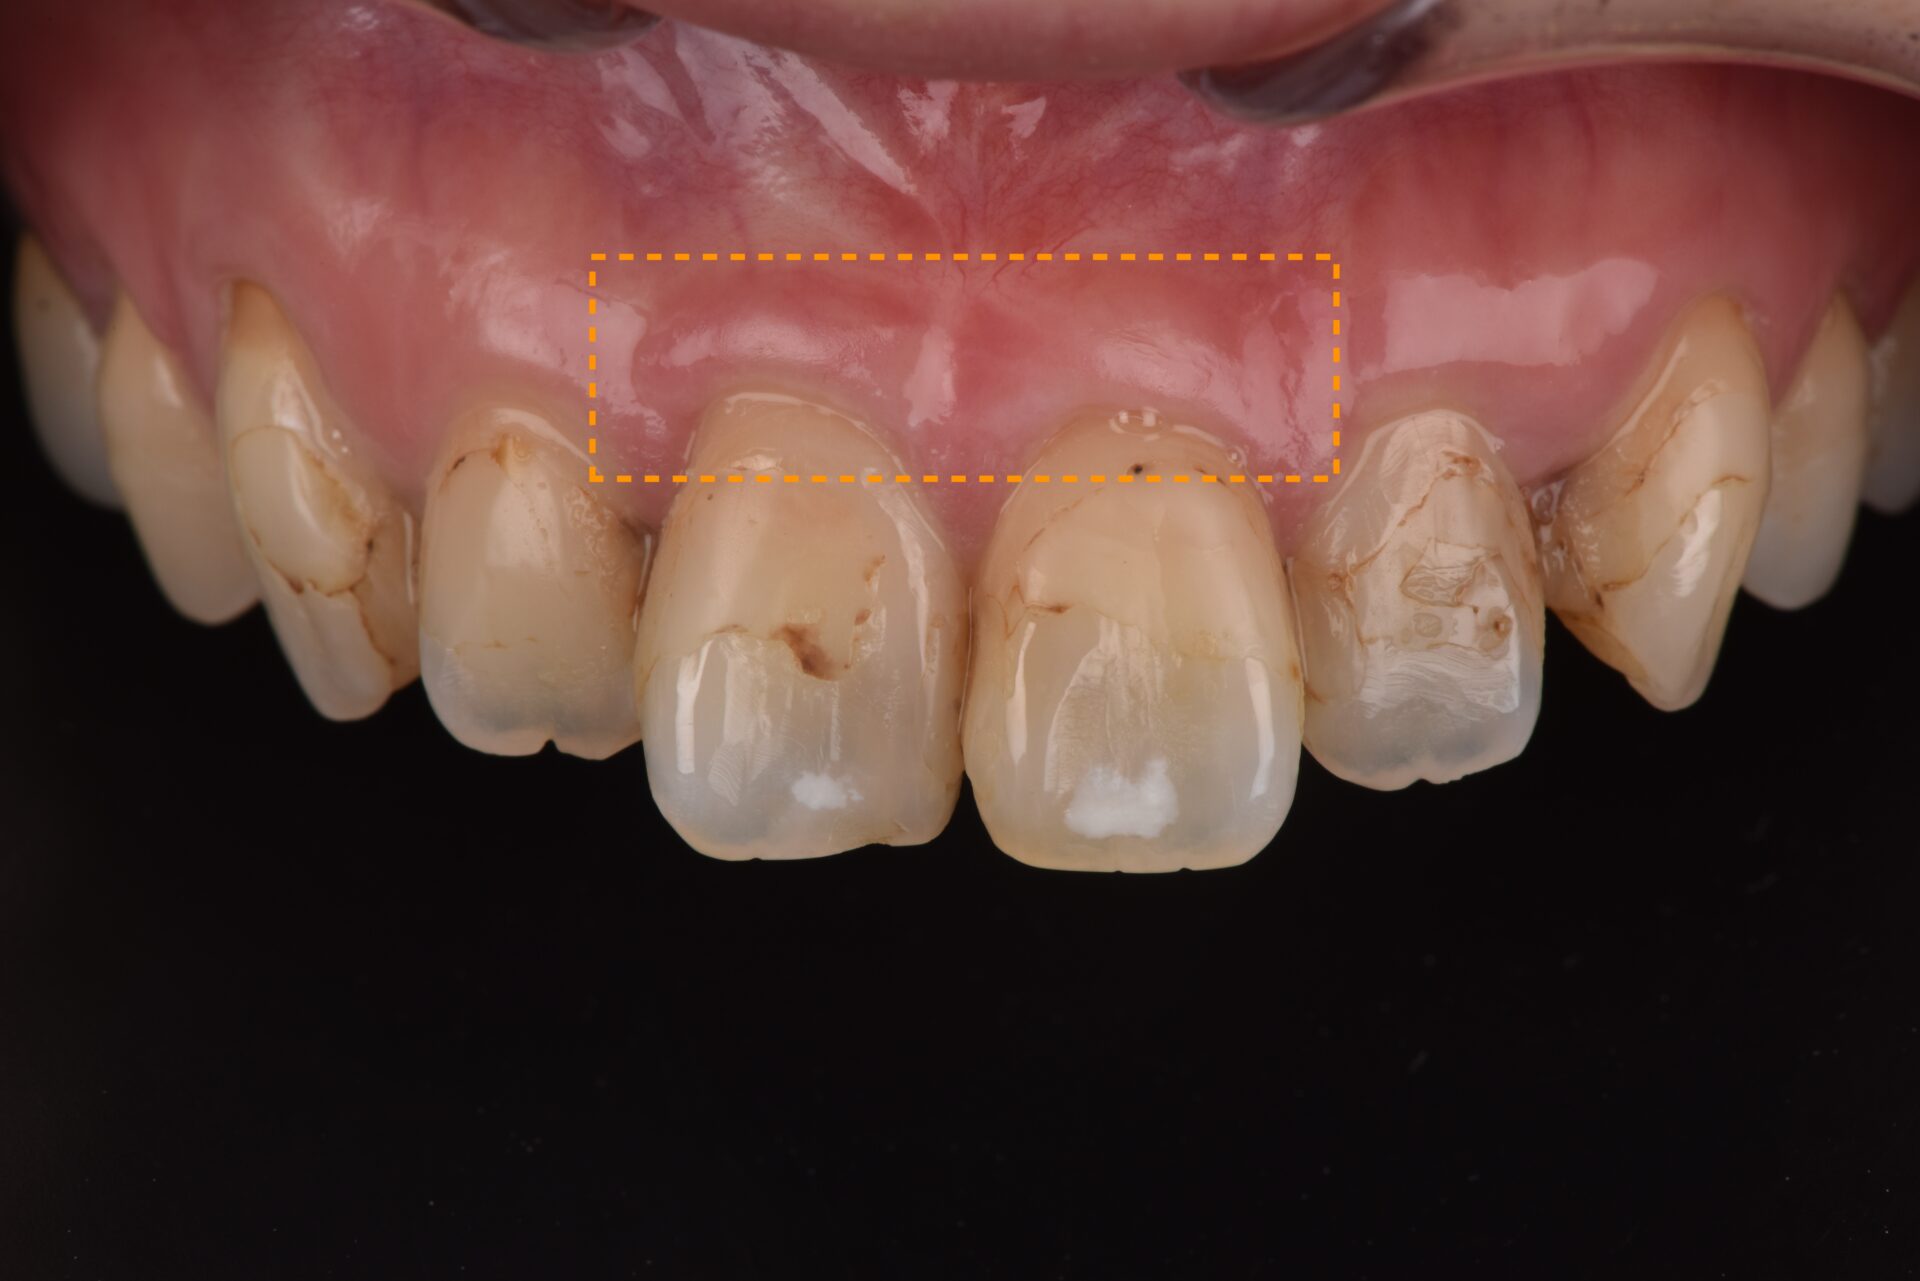

CTG(結合組織移植術) 臨床例②

矯正治療後、下顎前歯部の歯肉が退縮して歯根が露出し、見た目と機能の両面でお悩みでした。歯肉は非常に薄く、付着歯肉も不足しており、ブラッシング時に傷つきやすく、清掃が困難な状態でした。そのため、炎症を繰り返しており、審美的にも不均衡が見られました。長期的に歯周組織を安定させるには、外科的な介入が必要と判断しました。

3か月後には付着歯肉の幅がしっかりと増加し、炎症が改善。歯肉の厚みと付着歯肉の幅が増加し、ブラッシング時の出血や痛みが改善され、審美的に自然で調和の取れた歯肉ラインを獲得。長期的に安定した歯周組織環境を確立することができた。

術前3ヶ月